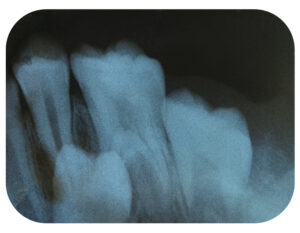

当院の強みは、咬み合わせ、矯正、補綴を総合的に診ることができる点にあります。美しい歯並びだけでは良い咬み合わせとは言えません。顎の動きに沿った機能的な咬み合わせを治療目標に掲げ、顎関節の機能を検査しながら、非抜歯矯正や歯の形を整える治療を行います。これにより、患者様一人ひとりのニーズに応じた、より効果的で包括的な治療を提供します。